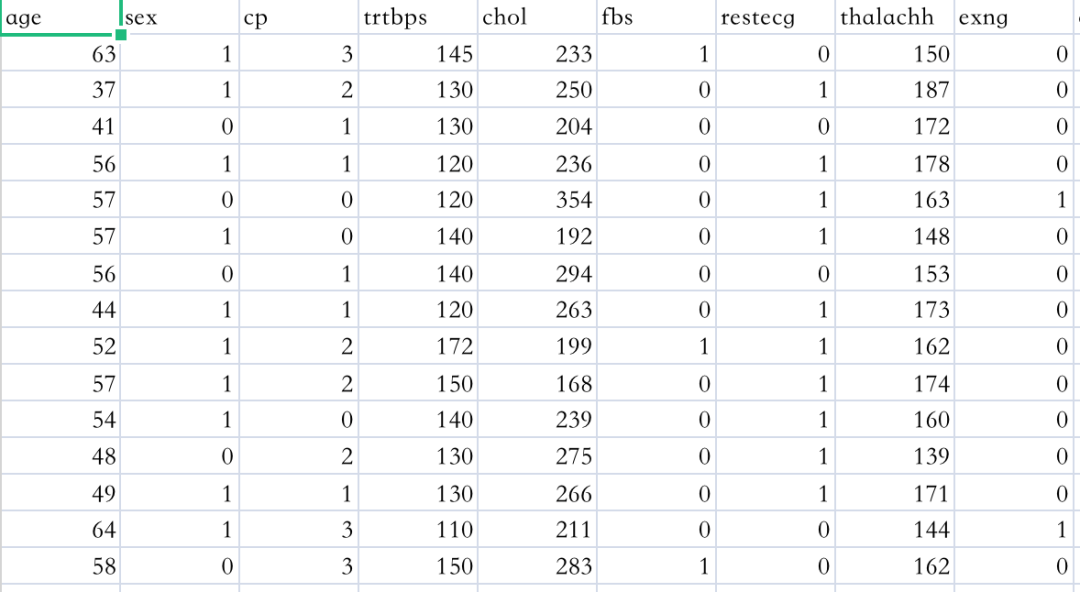

心脏病发作分析和预测数据集

数据集下载地址:http://m6z.cn/6ikH8v

本数据集含有303名心脏病患者的数据。